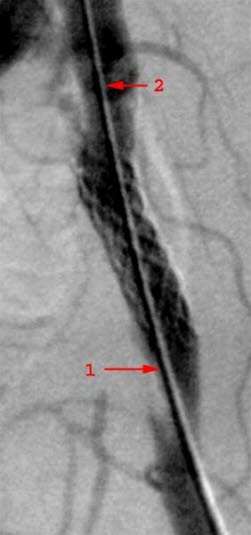

Bekkenarterie med innsatt stentRøntgenleger og organspesialister (eks. kardiologer, gastroenterologer, urologer) utfører et økende antall behandlinger som ledd i sine undersøkelser. Ofte dreier det seg om å vide ut en trang eller lukket blodåre, gallegang, urinleder. Enten punkteres det aktuelle området direkte, eller det nås via et kateter som føres gjennom blodårer, galleganger, urinveier etc. Sjeldnere kan inngrepet innebære å tømme en byll eller andre væskeopphopninger, eller det kan være å ta en vevsprøve fra et indre organ.

Blodårestenter og filtre

Stenter er utvidbare metallsylindre som er foldet sammen slik at de kan innføres gjennom en arterie eller vene. Ballongekspanderbare stenter er stive og plasseres ved å pumpe opp en ballong som stenten ligger rundt. Selvekspanderbare stenter ligger sammenfoldet i en plasthylse og folder seg selv ut når denne hylsen trekkes tilbake. Propper i blodkar kan også hentes (suges) ut ved hjelp av kateter som føres fram til det tilstoppede området.